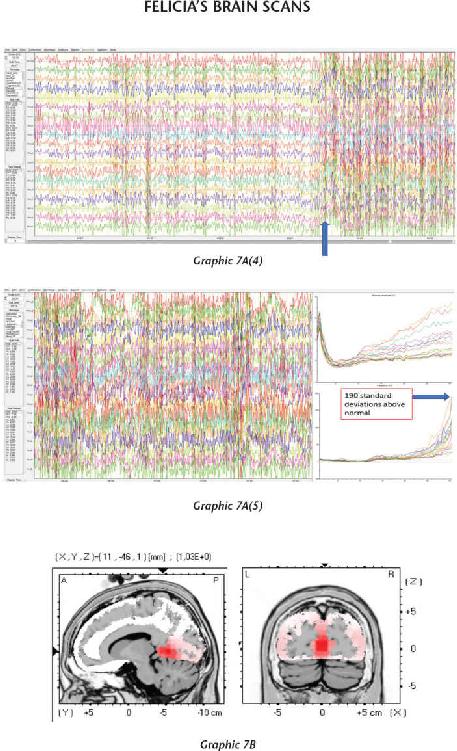

We have thousands and thousands of brain scans that prove those changes were not just imagined in their minds but actually took place in their brains. Several of the students we measured accomplished those changes within four days (the length of our advanced workshops). The scientific teams I’ve assembled have taken brain scan recordings using quantitative electroencephalogram (EEG) measurements before and after workshops as well as real-time measurements during the meditations and practices themselves. I was not only impressed with the changes, but shocked by them—they were that dramatic.

At the end of 2013, something mysterious started occurring. We started seeing brain scan recordings that puzzled the researchers and neuroscientists who came to our events to study my work. The high amount of energy in the brain that we were recording while a student was in certain meditations had never been recorded up until this point. And yet we were seeing these off-the-charts readings again and again.

When we interviewed the participants, they reported that their subjective experience during the meditation was very real and mystical, and that this either profoundly changed their view of the world or dramatically improved their health. I knew in those moments that these participants were having transcendental experiences in their inner world of meditation that were more real than anything they had ever experienced in their outer world. And we were capturing those subjective experiences objectively.